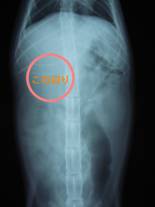

腹部レントゲン検査を行い、胃が何かに押されているような様子を確認。超音波検査も行い、腹腔内に腫瘤を確認。手術を行った。

レントゲンで確認した位置に、大きな腫瘤を認める。